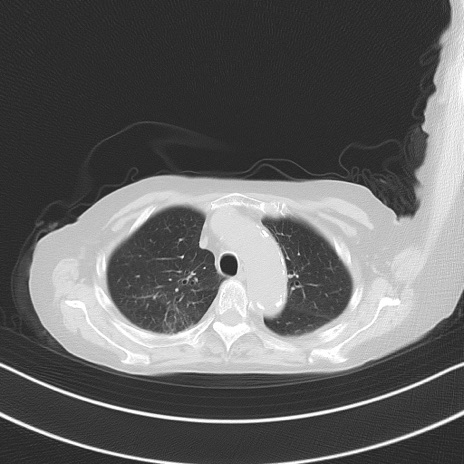

他院CT